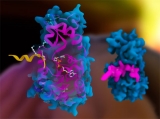

El dominioma humano revela la causa raíz de las enfermedades hereditarias

Investigadores del Instituto Wellcome Sanger y el CRG de Barcelona descubrieron que la inestabilidad proteica es uno de los principales impulsores de la formación de cataratas hereditarias y contribuye en algunas enfermedades neurológicas, del desarrollo y musculares.